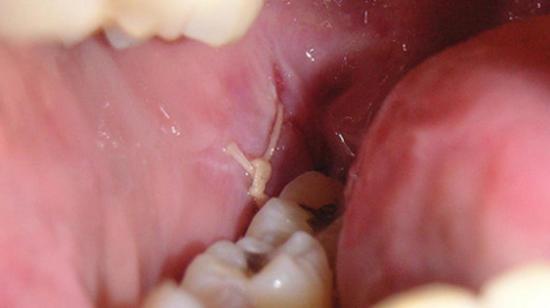

Infected Wisdom Tooth Might Be Pericoronitis Best Home Remedies

Infection After Extraction 3 Weeks Ago Neurotalk Support Groups